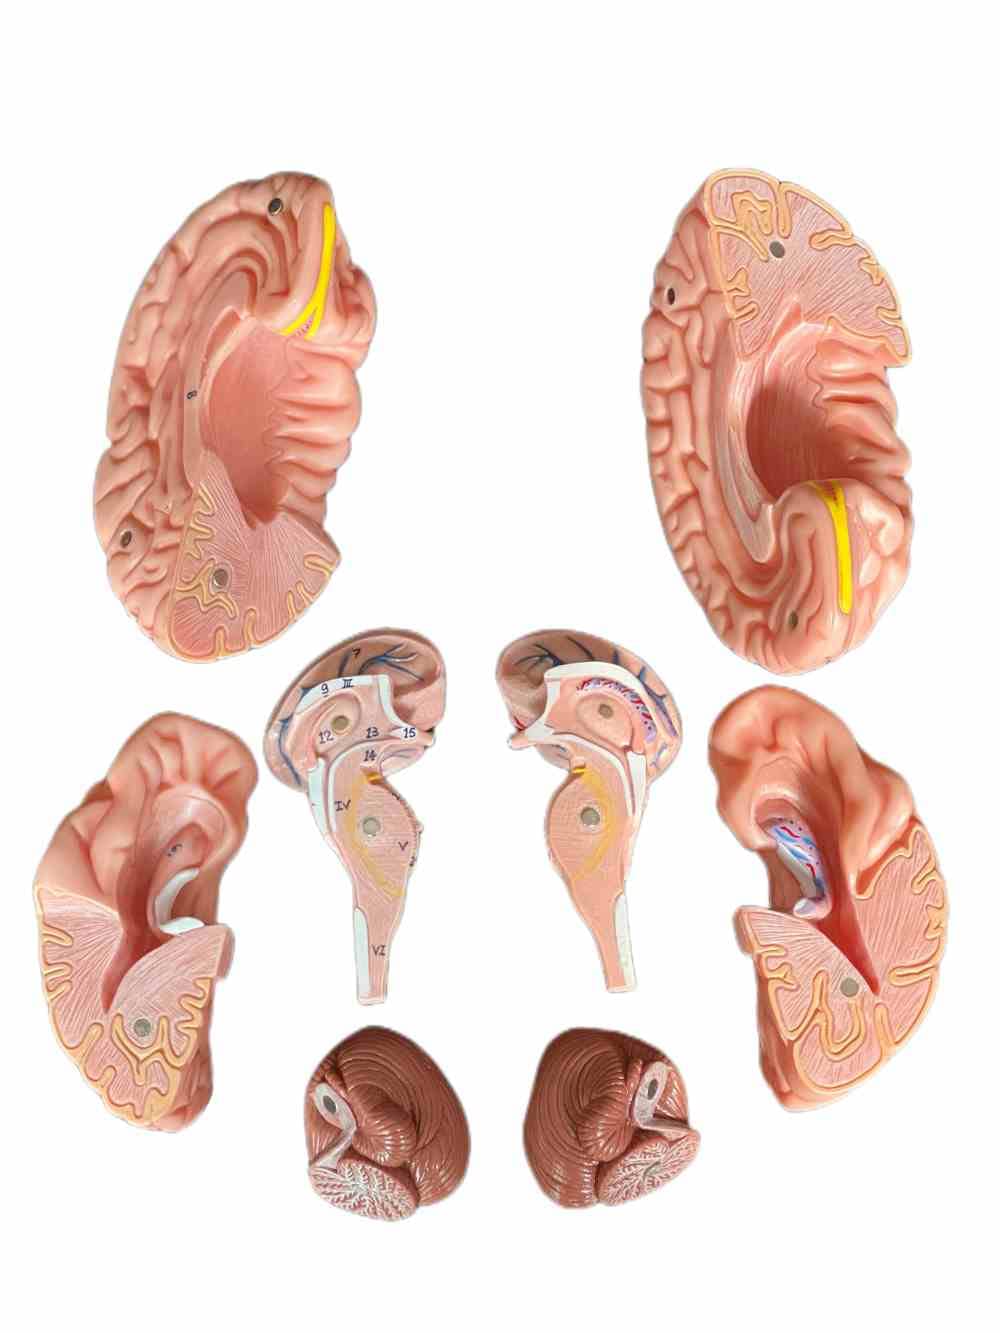

This model is cast from a high-quality original specimen. The classic skull is medically detailed in structure. It has highly accurate representation of the fissures, foramina, processes, sutures etc. Skull is 3-part: Skull Cap, Base of Skull and Mandible. The mandible is articulated on springs to demonstrate natural movements. Use this unique transparent replica of the human skull to study internal structures that otherwise are visible only through x-ray images. Brain separates into 8 parts: frontal and parietal lobes (2), temporal and occipital lobes (2), medulla (2), cerebellum (2). Structures are shown in great detail with about 30 features marked with numbers. Number key is provided. A great addition to any educational collection. Size: Life size Measurement: 22X13X17cm Weight: 2 kgs Material: high quality PVC

- The brain can be disassembled into 8 parts.